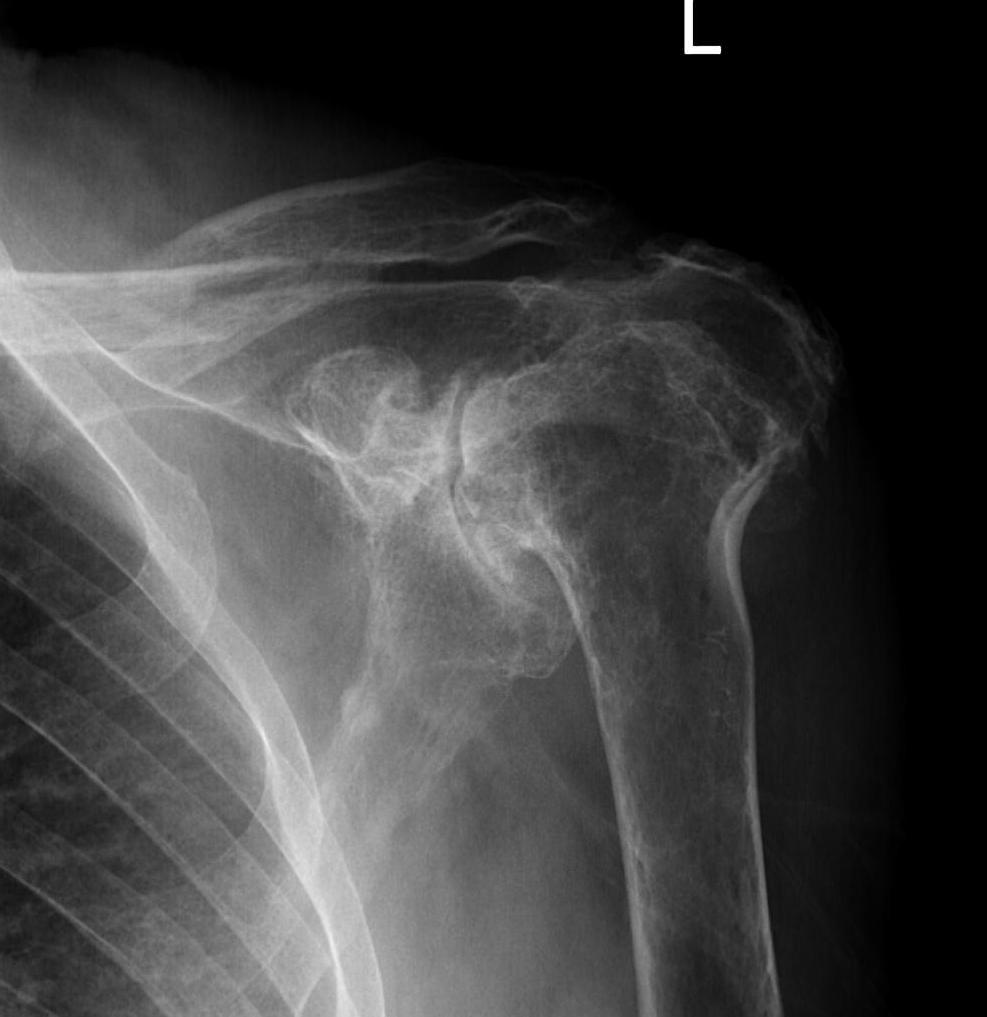

Destructive RA

Glenoid deficiency

Levigne and Franceschi Classification

Three main patterns

| Type 1 | Type 2 | Type 3 |

|---|---|---|

|

Upward migration Superior glenoid wear |

Concentric medial migration Deficient medial bone stock |

Destructive |

Due to rotator cuff insufficiency Most common pattern |